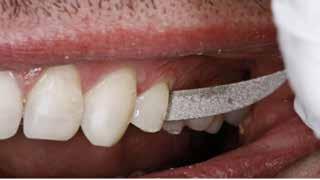

Fig. 3. Kofferdam blev anlagt sektionsvis for at opnå god fugtighedskontrol. Fig. 3. Rubber dam was applied section wise to achieve appropriate moisture control.

Fig.

okklusal-vertikale dimension. De afficerede dentinoverflader blev ridset i overfladen med en grov diamant, men derudover blev der ikke foretaget nogen form for kavitetspræparation, da intentionen var at gennemføre en minimalt invasiv behandlingstilgang. Kofferdam blev anlagt i hvert arbejdsfelt (Fig. 3) og adhæsivet påført med en æts-og-skyl-strategi (ætsning af emalje og dentin, primer, adhæsiv). Derefter blev tænderne bygget op med en mikrohybrid komposit for at genskabe tandens naturlige form (Fig. 4). I underkæbefronten blev der kun lagt et tyndt lag med komposit pga. pladsmangel. Efter omhyggelig pudsning og polering havde patienten okklusion på samtlige tænder og var tilfreds med både funktion og æstetik.

Restaurering af et slidt tandsæt ved hjælp af adhæsiv teknik og direkte komposit er tidkrævende og teknisk udfordrende. Det kræver gode procedurer at opretholde en nødvendig og god intraoral fugtighedskontrol over længere tid. Anvendelse af kofferdam er i disse tilfælde et godt hjælpemiddel, som giver god isolation af arbejdsfeltet. Ulemperne er, at operatøren mister overblikket over hele tandsættet og ikke er i stand til at kontrollere okklusion og relation til andre tænder undervejs i behandlingen. Løsningen kan da være at montere kofferdamdugen og restaurere tænder sektionsvis med kontrol af relationer indimellem (Fig. 3).